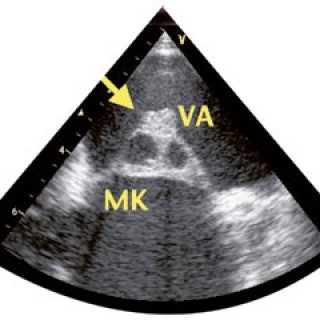

En 52 år gammel etnisk norsk mann ble innlagt i psykiatrisk akuttavdeling etter noen få uker med kraftig økende aktivitetsnivå. Han hadde vist markant endret atferd – blant annet hadde han satt seg fore å sykle åtte mil i kuldegrader og slaps. Ved innleggelsen var han irritabel og snakket fort og nærmest usammenhengende. Somatisk status presens ved innkomst samt orienterende nevrologisk status var normale. Vanlige blodprøver ved innleggelse, inklusive Hb, SR, hvite blodceller, kreatinin, natrium, kalium, ALAT, ASAT, ferritin, folat, kobalamin, FT4, TSH, var alle innenfor referanseområdet...